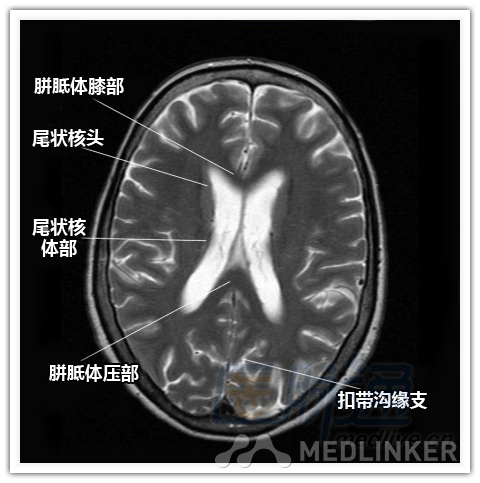

本文将对不同横断位的脑部MRI图像进行标示,主要讲解内容是脑部基本解剖。脑部横断位解剖,尤其是内囊层面的影像学解剖一直是一大重点,一起来学习一下。 现在是内囊层面了,同志们准备好了吗? 本文转载自医脉通。 声明:本文转载是出于提供更多信息以参考使用或学习、交流之目的,不用于商业用途。转载无意侵犯版权,如转载文章涉及您的权益等问题,请作者速来告知,我们将尽快做删除处理。